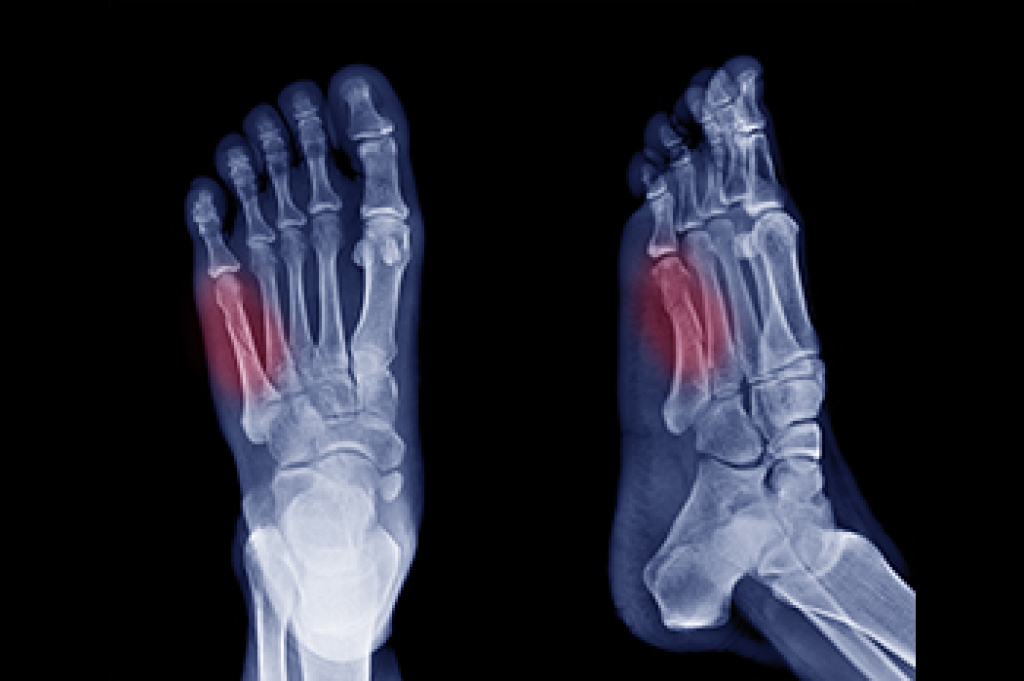

Pain on the outer side of the foot can sometimes signal an avulsion fracture, also called a pseudo Jones fracture. This type of injury affects the base of the fifth metatarsal, which is the long bone below the pinky toe. The fracture happens when a tendon pulls a small piece of bone away from its attachment. The injury can occur after a sudden twist, roll, or direct impact to the ankle or foot. People typically notice sharp pain, swelling, and tenderness near the outer edge of the foot, making walking or bearing weight difficult. Because this fracture can be mistaken for a sprain or a more serious type of fracture, an accurate diagnosis is important. A podiatrist can perform an exam, order X-rays, and recommend the best course of treatment, including immobilization or, in some cases, surgery. If you are experiencing outer foot pain, it is suggested that you make an appointment with a podiatrist for a diagnosis and treatment.

A broken foot is caused by one of the bones in the foot typically breaking when bended, crushed, or stretched beyond its natural capabilities. Usually the location of the fracture indicates how the break occurred, whether it was through an object, fall, or any other type of injury.

Treatment for broken bones varies depending on the cause, severity and location. Some will require the use of splints, casts or crutches while others could even involve surgery to repair the broken bones. Personal care includes the use of ice and keeping the foot stabilized and elevated.